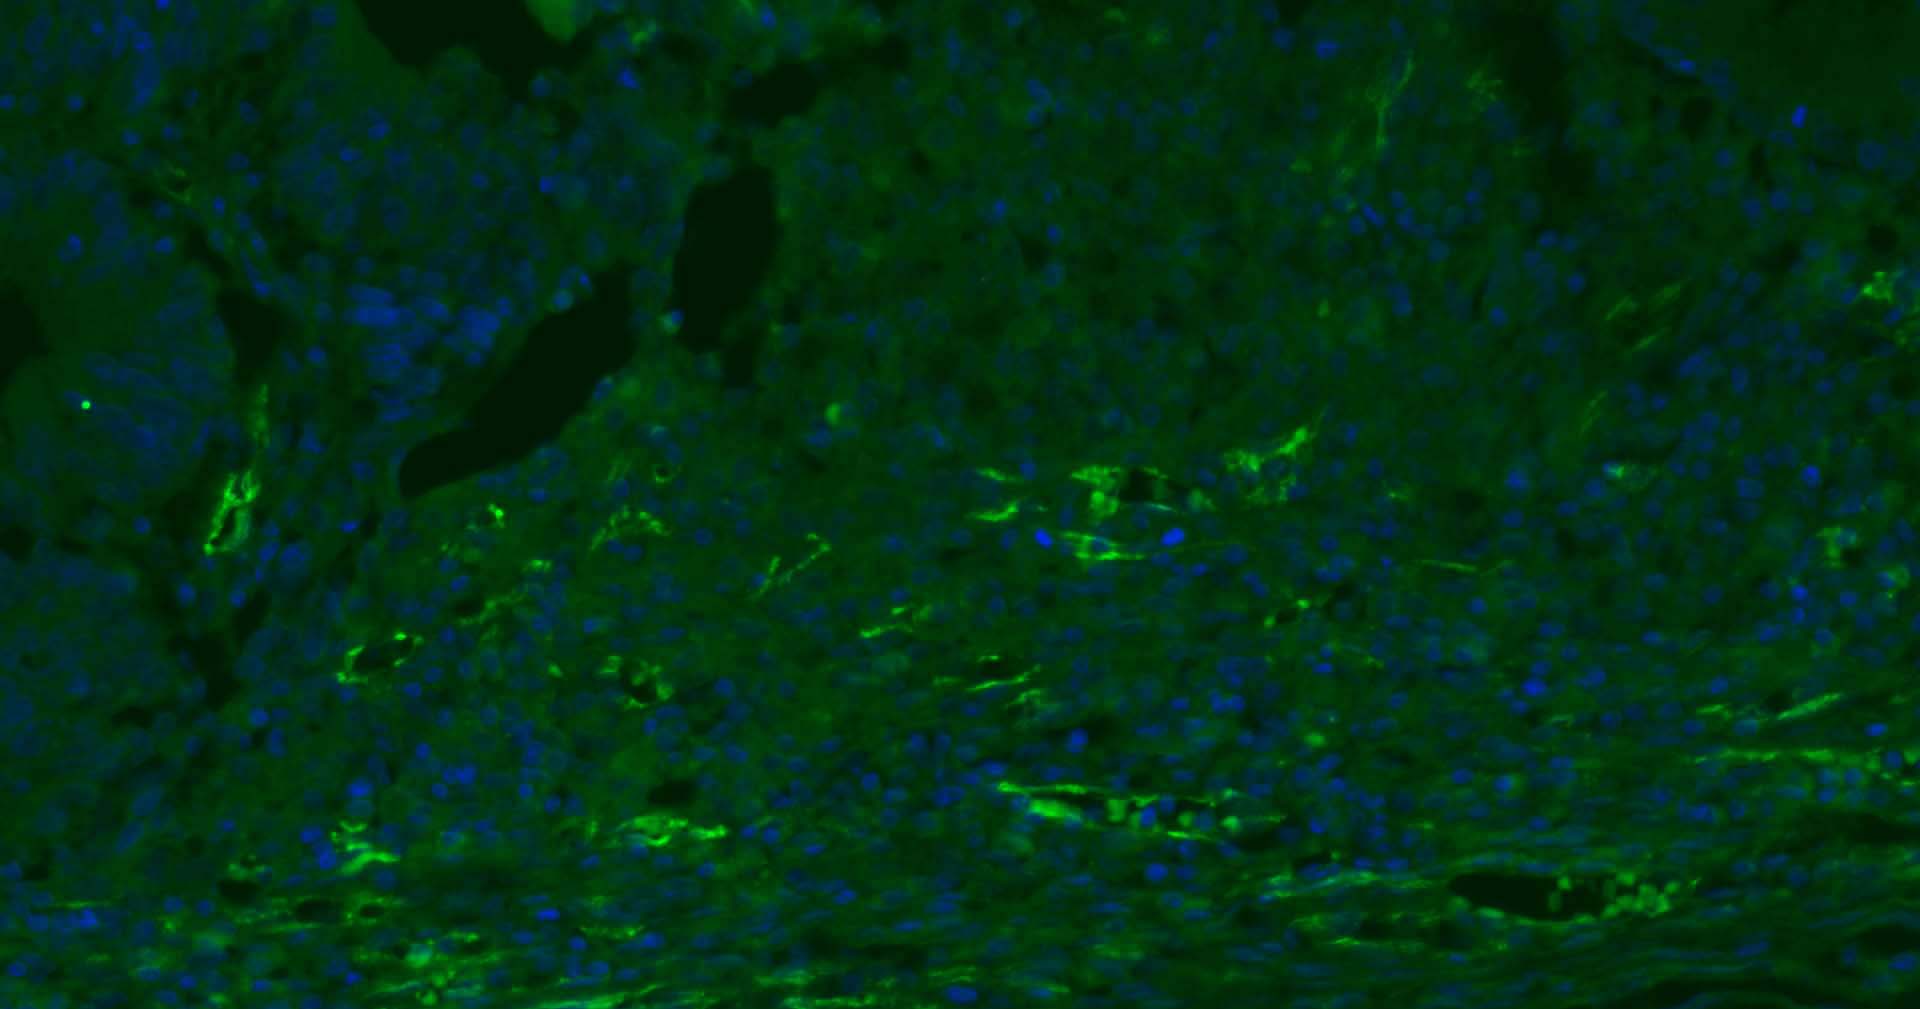

Paraformaldehyde-fixed, paraffin embedded Human Tonsil; Antigen retrieval by boiling in sodium citrate buffer (pH6.0) for 15 min; Antibody incubation with CD31 Monoclonal Antibody, Unconjugated (bsm-10825M) at 1:200 overnight at 4°C. Followed by conjugated Goat Anti-Rabbit IgG antibody (green, bs-0296G-BF488), DAPI (blue, C02-04002) was used to stain the cell nuclei.